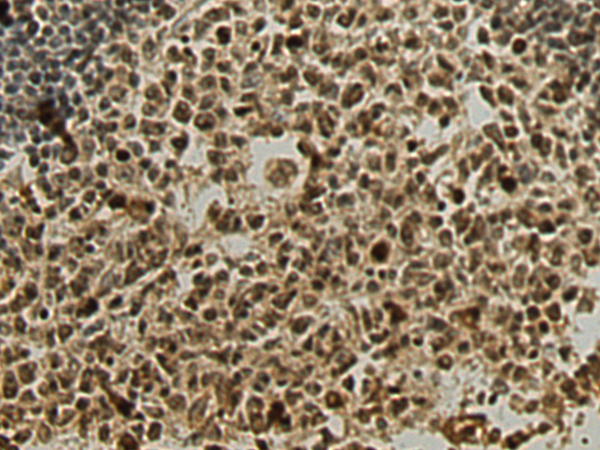

The image is immunohistochemistry of paraffin-embedded Human tonsil tissue using (ntibody) at dilution 1/120.

,

The image is immunohistochemistry of paraffin-embedded Human gastric cancer tissue using (ntibody) at dilution 1/120.